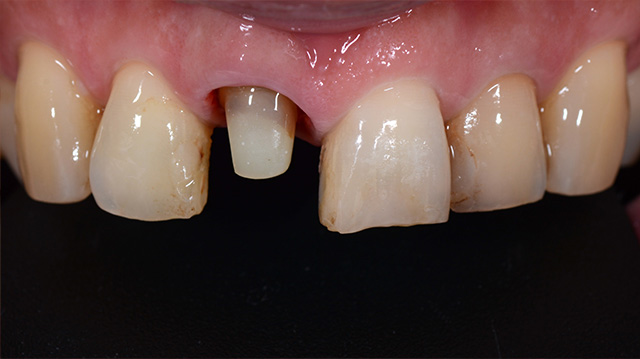

| 年代・性別 | 50代 男性 |

|---|---|

| 主訴 | 転倒して歯が割れた |

| 治療回数 | 3回 |

| 治療期間 | 約1ヶ月 |

| 費用 | 仮歯 5,500円 ジルコニアクラウン 176,000円 |